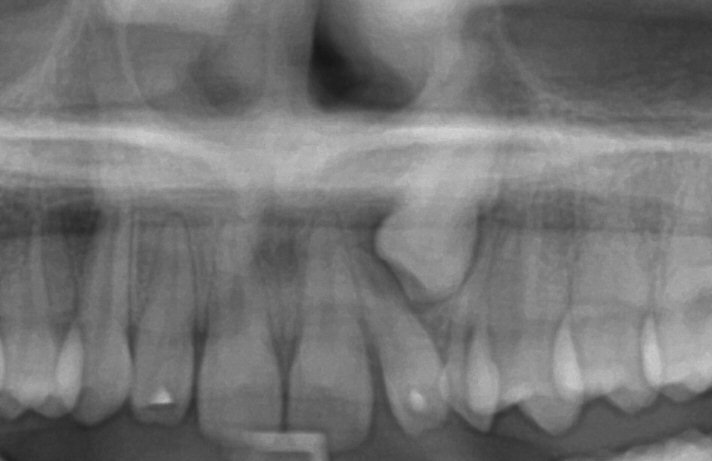

Fig. 13 Initial panoramic radiograph (cropped) of impacted lower left canine (at 16 y.o.)

© Copyright 2007-2014, Vu Orthodontics. All rights reserved.